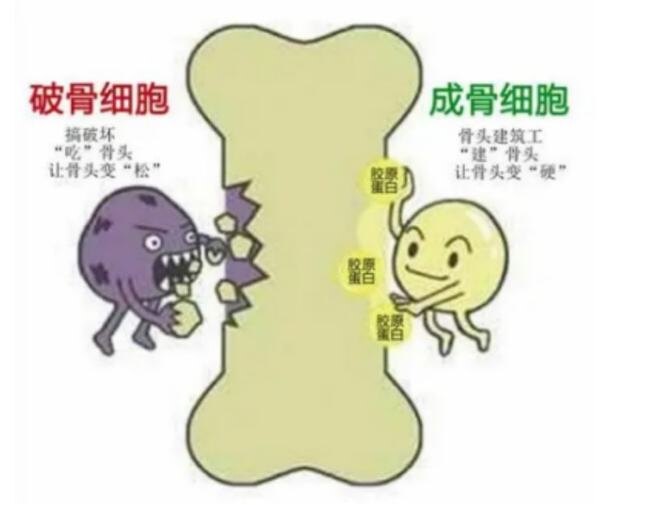

破骨细胞的作用是吞噬吸收旧骨、病骨和死骨。骨原细胞是成骨细胞的预备队,随时可以转变为成骨细胞。成骨细胞的主要功能是分泌I型胶原蛋白,用来填充被破骨细胞“吃”掉骨质形成的“骨坑”,修复骨质。同时还成骨细胞还分泌骨钙素。

破骨细胞和成骨细胞